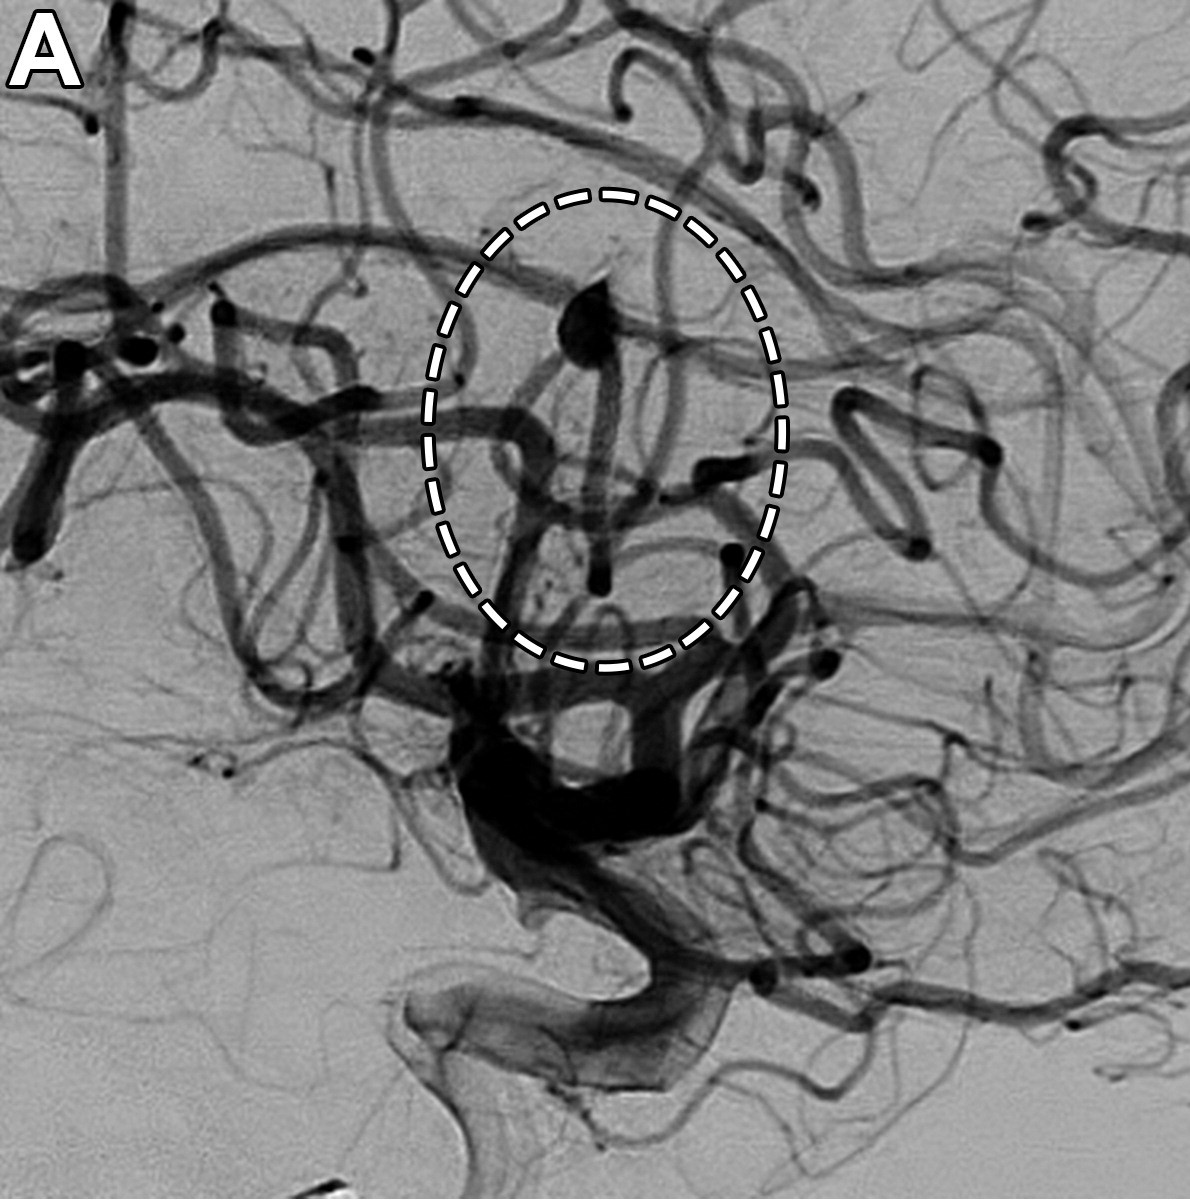

Angiografía por sustracción digital

Estándar diagnóstico para diagnóstico de aneurismas intravasculares rotos y no rotos, por su mayor precisión con respecto al TOF 3D y la capacidad de caracterización de pequeños vasos y perforantes; es insuficiente para aneurismas parcialmente trombosados y calcificados, requiriendo complementarse con otros métodos diagnósticos.

• Aneurisma o rotura del vaso: es la complicación más devastadora mayormente presenciada en procedimiento de angioplastia, se observa en imágenes de DSA como extravasación activa del material (hiperatenuante).